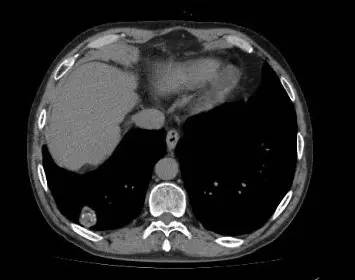

男,52岁,查体发现肺部病变

[影像描述]

右肺下叶结节样病变,内有钙化、脂肪成分,增强后可见轻度强化。

[检查结果]

右肺下叶错构瘤.

右肺下叶病变内有钙化、脂肪成分,典型爆米花样钙化,增强后可见轻度强化。